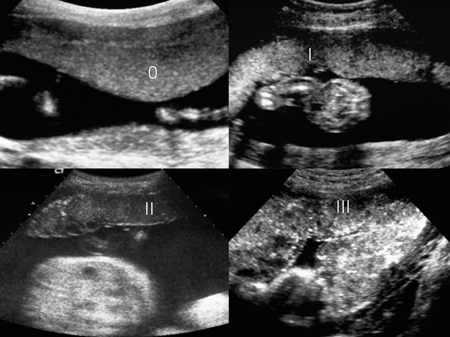

Με την πρόοδο της εγκυμοσύνης επισυμβαίνει φυσιολογική εναπόθεση ασβεστίου στο

πλακουντιακό παρέγχυμα, η οποία απεικονίζεται υπερηχογραφικώς ως λευκά στίγματα

(εικόνα 1). Για τη σταδιοποίηση της έκτασης των αποτιτανώσεων και της ωρίμανσης

του πλακούντα χρησιμοποιούνται οι βαθμοί 0, Ι, ΙΙ, ΙΙΙ, οι οποίοι έχουν τελικά

μικρή κλινική σημασία (πίνακας 1). Το κάπνισμα έχει συσχετισθεί με εκτεταμένες

αποτιτανώσεις του πλακούντα.(2)

Εικόνα 1. Στάδια ωρίμανσης

του πλακούντα.

| Πίνακας 1. Στάδια ωρίμανσης του πλακούντα. | ||||||||||

| ΣΤΑΔΙΟ

0 |

Στα τέλη του πρώτου έως αρχές δευτέρου τριμήνου, ομαλή εμβρυική επιφάνεια και ομοιογενούς υφής πλακουντιακό παρέγχυμα, χωρίς εισολκές. | |||||||||

Ι |

Περίπου στις 18-29 εβδομάδες κύησης, ελαφρές εισολκές της εμβρυικής πλακουντιακής επιφάνειας και διάσπαρτες μικρές υπερηχογενείς αποτιτανώσεις στο πλακουντιακό παρέγχυμα. | |||||||||

ΙΙ |

Περίπου από στις 30 έως 40 εβδομάδες κύησης, πιο έντονες εισολκές της πλακουντιακής επιφάνειας και πιο έντονες αποτιτανώσεις που ξεκινούν από τη μητρική επιφάνεια του πλακούντα και επεκτείνονται στην περιφέρεια των κοτυληδόνων. | |||||||||

ΙΙΙ |

Συνήθως στο τέλος της κύησης και στην παράταση, παρατηρείται στο 15% των κυήσεων μετά τις 36 εβδομάδες. Βαθιές εισολκές της πλακουντιακής επιφάνειας και έντονες αποτιτανώσεις, που ξεκινούν από τη μητρική επιφάνεια του πλακούντα και καταλήγουν στην εμβρυική επιφάνεια του πλακούντα, διαχωρίζοντας τελείως τις κοτυληδόνες. Επίσης, μπορεί να παρατηρηθούν και υποηχογενείς λίμνες στο κέντρο των κοτυληδόνων. | |||||||||